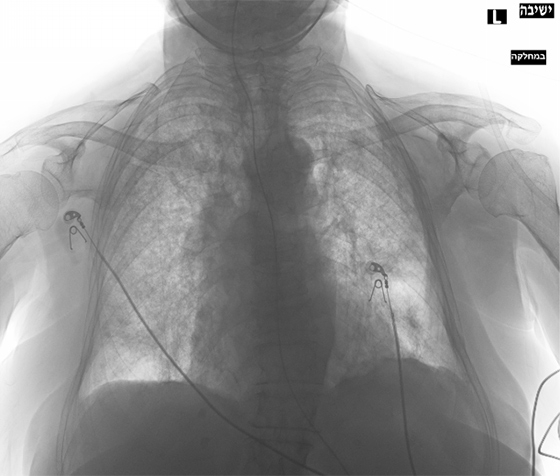

Этот цикл я писал, всматриваясь в медицинские снимки умирающего родного тела. Я пытался разглядеть его изнутри и осознать неосознаваемое: как это — постепенно умирать? Как отпустить, чем отстоять и куда его уложить, чтобы не было больно? В ужасе я наблюдал за расплывающимися узорами смерти, пока она не залила все живые уголки дряхлого тела. Снимки и тексты — свидетельства скрытого, немого страдания, которому я даю право быть увиденным и услышанным.

Это — кадиш по моей бабушке, которая умерла 18 января 2019 года. Была пятница, и похоронить ее нужно было до захода солнца — до начала Шаббата, который наступает в пятничный вечер. Кладбище было напротив больницы, через дорогу. Мы хоронили ее через три часа после смерти, не успев позвать ни родных, ни близких. Кадиш — это иудейская поминальная молитва. Для ее чтения необходим миньян — десять мужчин. Нас было меньше, поэтому хоронили без молитвы, спешно. Эти стихотворения — мой кадиш, который тогда мне произнести не дали, мое отпевание пустоты, что осталась после нее. В кадише использованы реальные медицинские материалы — рентгеновские снимки, УЗИ, КТ, ЭКГ — из истории болезни бабушки, с момента обнаружения рака и до самой смерти. Последняя кардиограмма была снята с мертвого тела. Так требовал больничный протокол.